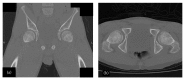

Traumatic dislocation of the hip in a child caused by trivial force for age

Traumatic hip dislocation in children has a relatively rare occurrence. There are some residual complications, such as avascular necrosis of the femoral head, growth disturbance caused by premature fusion, neurological injury, recurrent dislocation, and posttraumatic arthritis. There is no consensus in the literature about the period of non-weight bearing after reduction. A rare case of a 13-year-old boy of hip dislocation caused by trivial force for age is reported followed by review of the pediatric literatures with treatment recommendation.